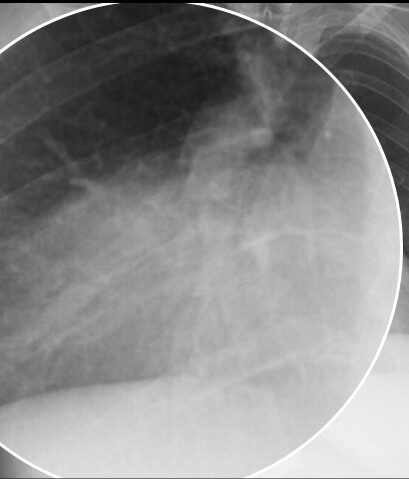

Radiologische Kontrolle von Herzschrittmachern und ICDs

Herzschrittmacher (SM) und implantierbare Cardioverter-Defibrillatoren (ICD) sind fester Bestandteil der Therapie von Herzrhythmusstörungen. Die Radiologie spielt dabei eine zentrale Rolle […]